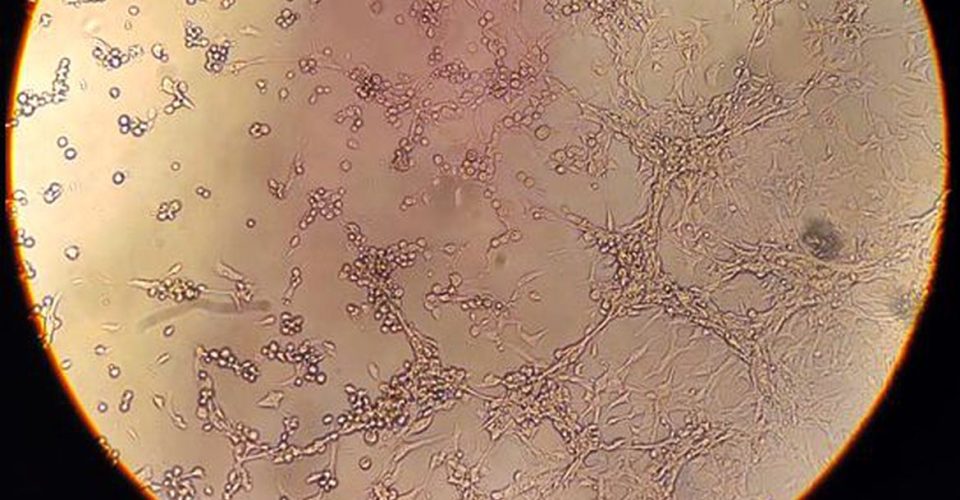

A varíola dos macacos é transmitida pelo vírus monkeypox, que pertence ao gênero orthopoxvirus